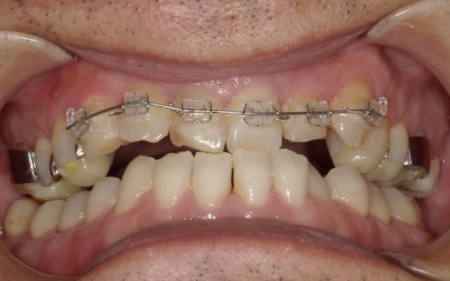

40代男性 虫歯治療やインプラント治療で口腔内全体を修復したあと部分矯正で噛み合わせを改善した症例

拝見したところ、複数の歯に虫歯が見られました。また、過去に治療した詰め物や被せ物が合わなくなっている部分や、歯が欠損している部位もあります。

・前歯の噛み合わせ

下前歯が上前歯より前に出ている「反対咬合(こうごう)」で、将来的に歯や顎への負担が生じるリスクがあります。

前歯の噛み合わせ治療では、上顎の内側に歯を内側から動かす装置「リンガルアーチ」を装着します。併せて、上前歯の表面に「ブラケット」と呼ばれるボタン状の装置を接着し、そこにワイヤーを通して歯を動かす「マルチブラケット装置」を用いて部分矯正を行いました。